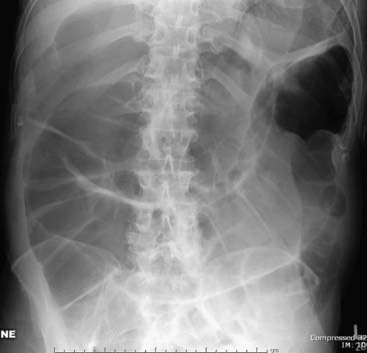

There is usually gas in the rectum or sigmoid in a localized ileus (Fig. 14-1).

image

Figure 14-1 Sentinel loops from pancreatitis.

A single, persistently dilated loop of small bowel is seen in the left upper quadrant (solid white arrows) on both the supine (A) and prone (B) radiographs of the abdomen. A sentinel loop or localized ileus often signals the presence of an adjacent irritative or inflammatory process. This patient had acute pancreatitis.